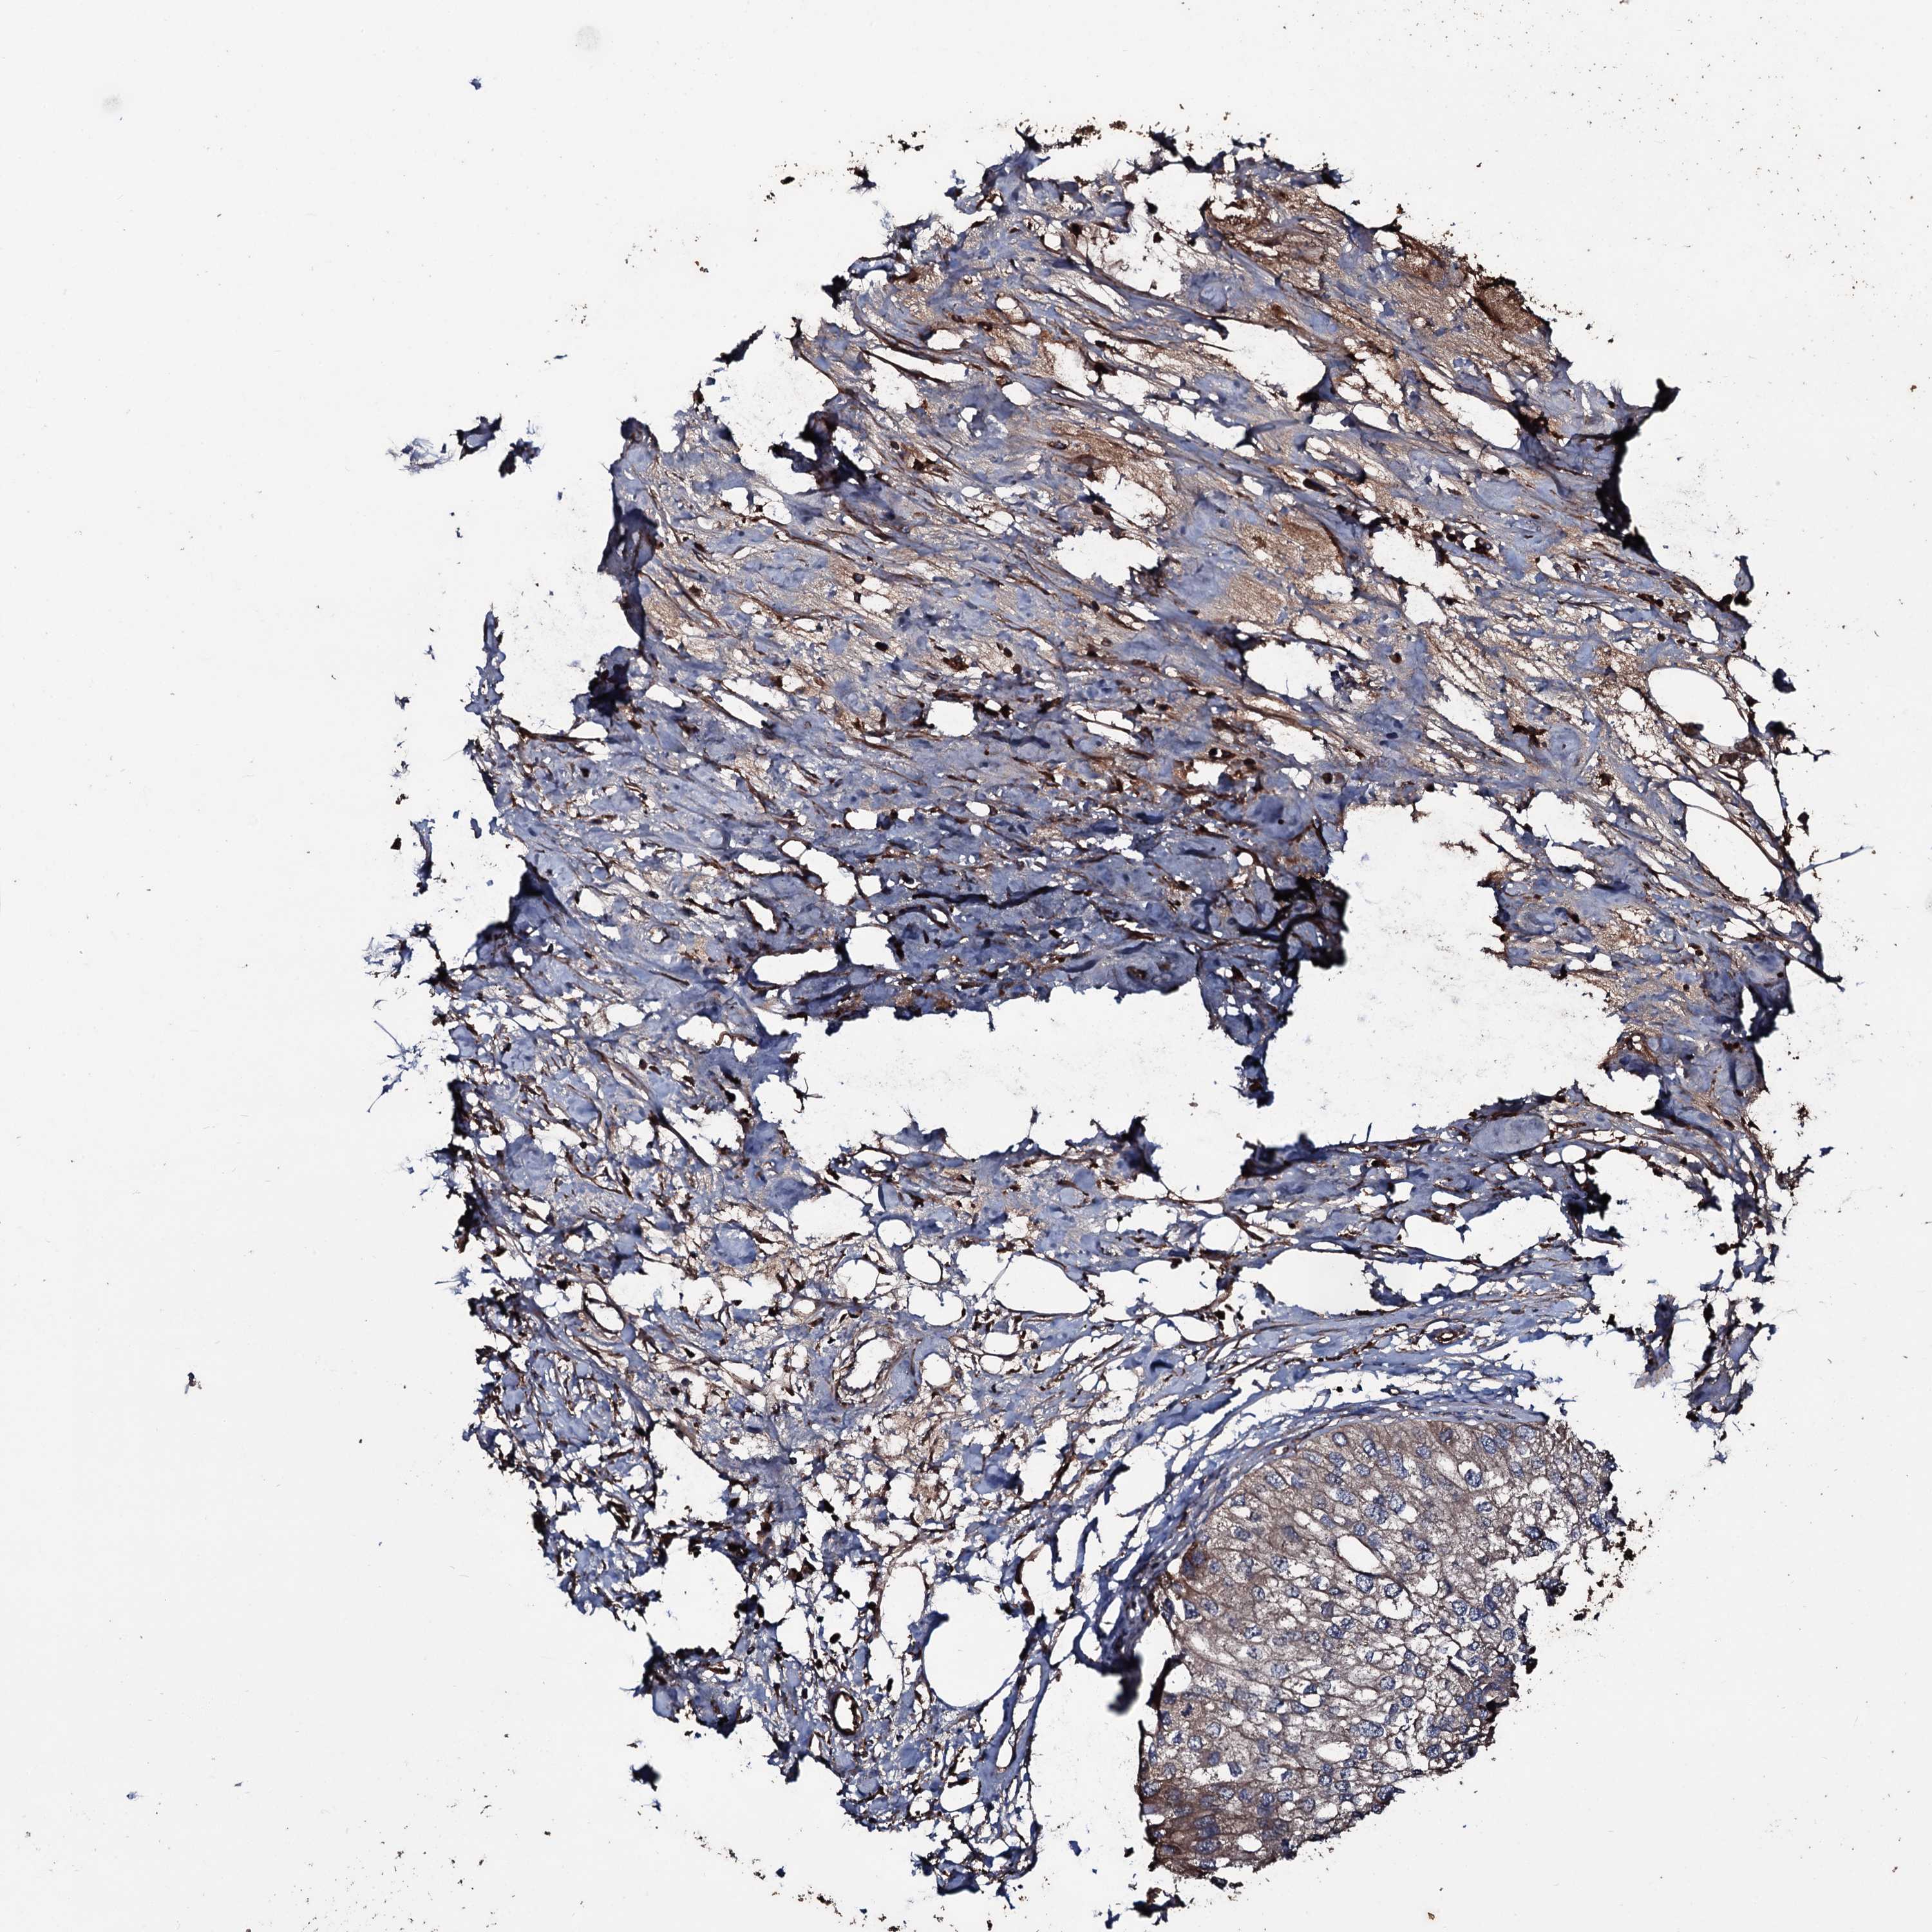

UROTHELIAL CANCER - Protein expressioni

A mouse-over function shows sample information and annotation data. Click on an image to view it in a full screen mode. Samples can be filtered based on level of antibody staining by selecting one or several of the following categories: high, medium, low and not detected. The assay and annotation is described here.

Note that samples used for immunohistochemistry by the Human Protein Atlas do not correspond to samples in the TCGA dataset.

Antibody stainingi

Antibody staining in the annotated cell types in the current human tissue is reported as not detected, low, medium, or high, based on conventional immunohistochemistry profiling in selected tissues. This score is based on the combination of the staining intensity and fraction of stained cells.

Each image is clickable and will lead to virtual microscopy that enables deeper exploration of all samples and also displays staining intensity scores, fraction scores and subcellular localization as well as patient and tissue information for each sample.

Antibody HPA041244

Staining

High

Medium

Low

Not detected

Intensity

Strong

Moderate

Weak

Negative

Quantity

>75%

75%-25%

<25%

None

Location

Nuclear

Cytoplasmic/membranous

Cytoplasmic/membranous,nuclear

Urothelial carcinoma, High grade

Urothelial carcinoma, Low grade